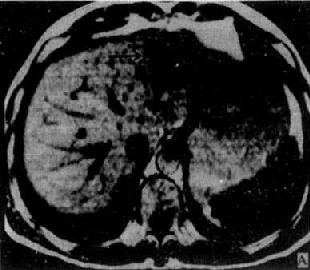

肝癌

图4-3-6 肝癌(MRI)

A、T1WI肝右叶可见大块较低信号区,其内信号不均,轮廓不规

则(↓)。门静脉内可见相同信号强度影像,为癌栓所致(↓)

B、T2WI上述稍低信号区成为稍高信号区(↓),门静脉内癌栓的信

号也增强(↓)